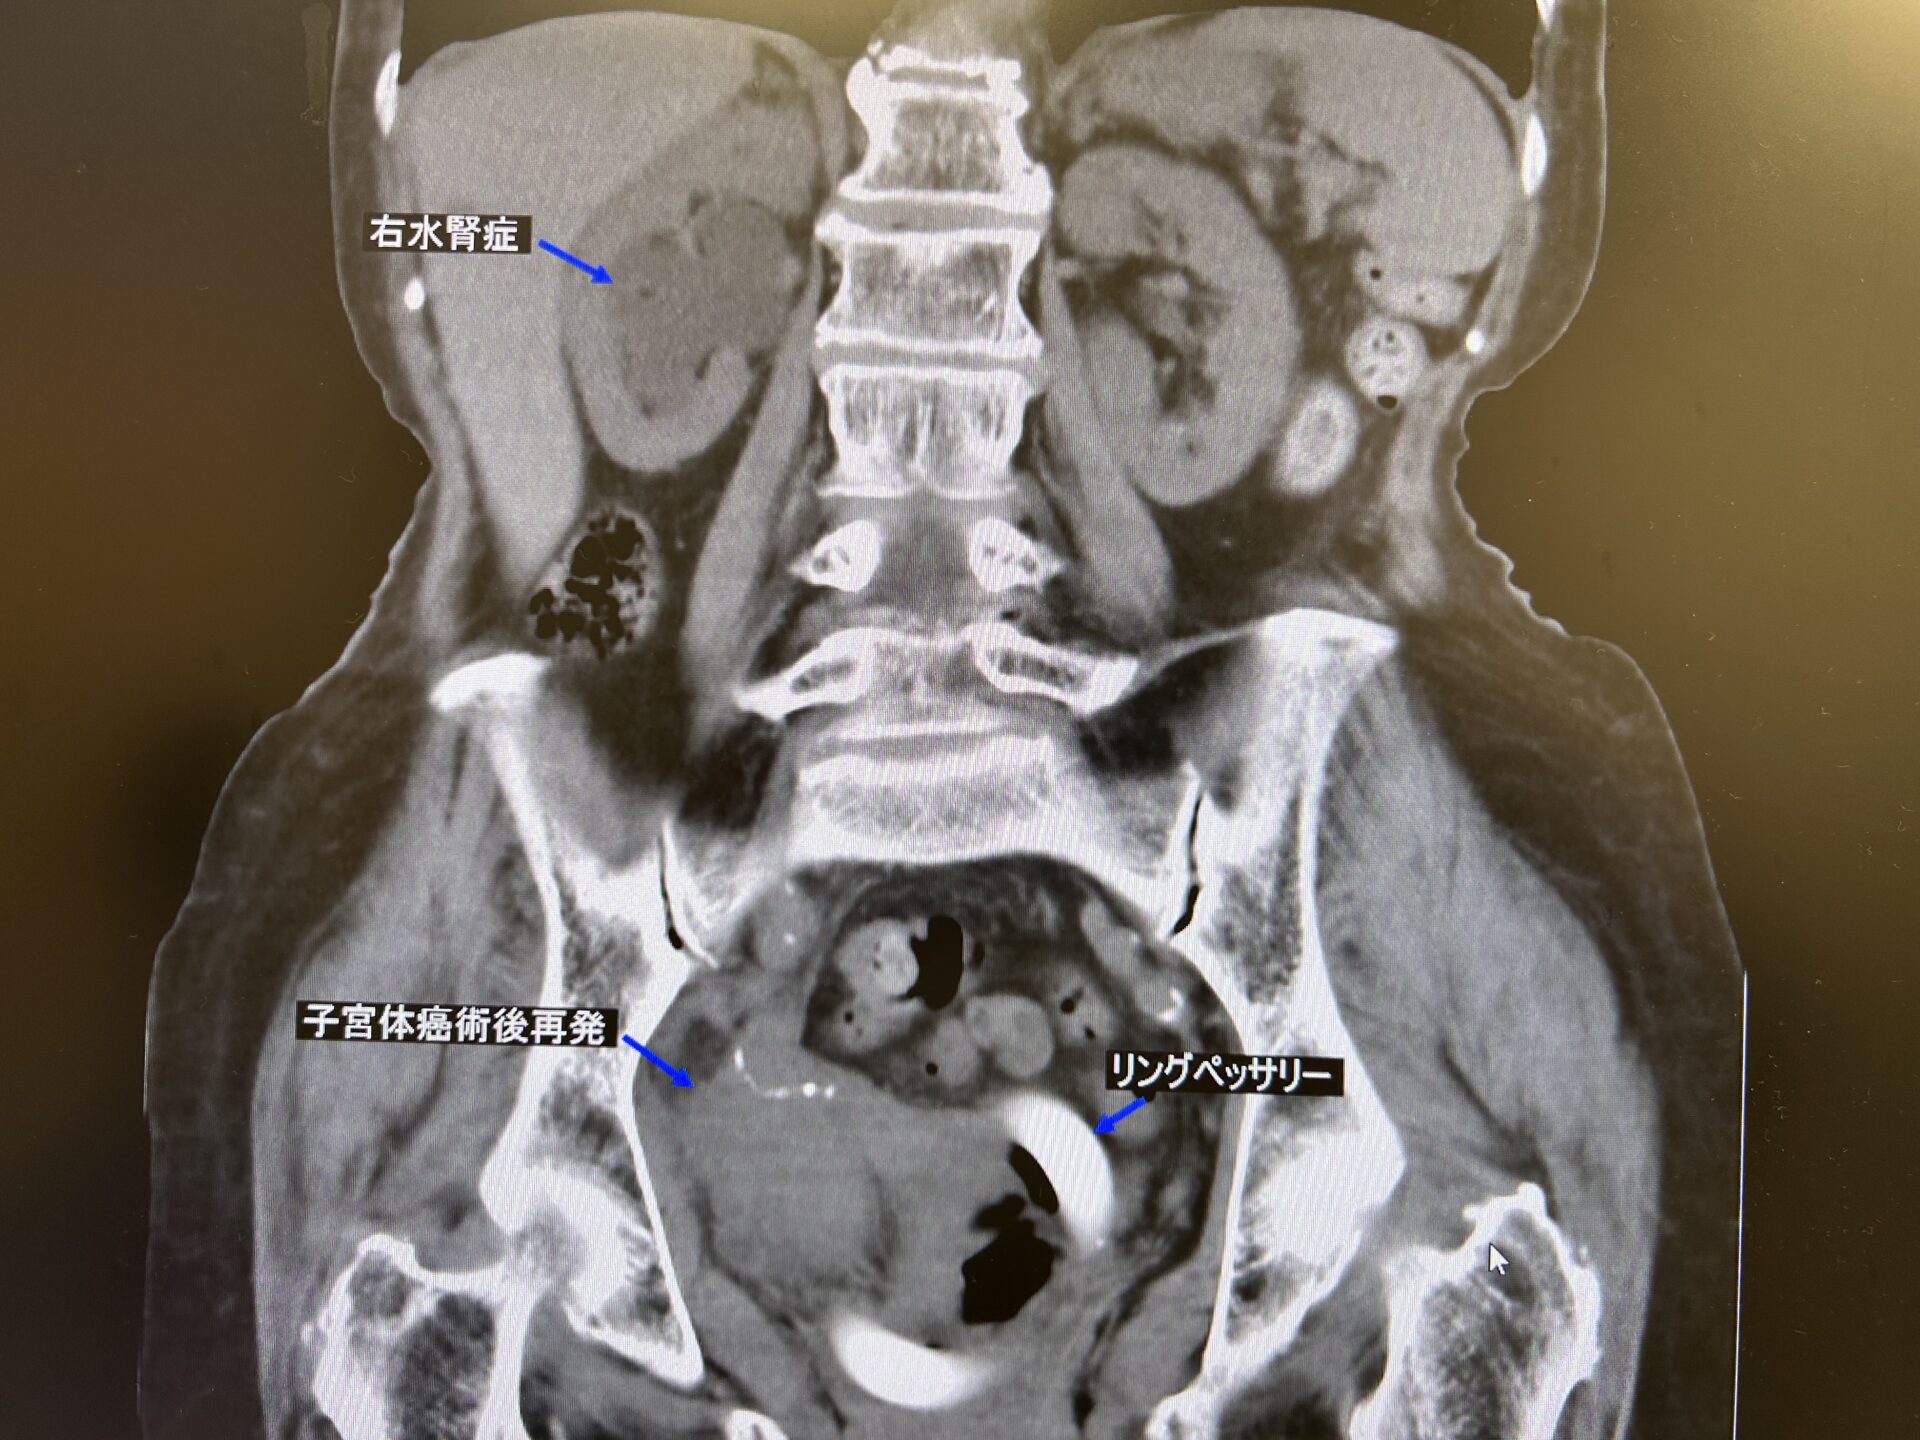

エコーでは実際の閉塞機転までは尿管を追う事が出来ないため、後日CT検査を行うこととしました。すると、CT上では骨盤内右側に手術痕とその周囲を取り巻くように腫瘤形成をなしており、また、膀胱への浸潤も来しているようにも見えます。ここが、右下部尿管を圧排もしくは浸潤して閉塞機転となっていると考えられました。

【CT冠状断像:子宮体癌術後局所再発と考えられる腫瘤形成および右水腎症】

念のために尿路由来ではない事を証明するために膀胱鏡と尿細胞診も検査することとしました。結果は尿細胞診classⅡ(陰性)、膀胱鏡所見でも右尿管口は確認出来るも膀胱粘膜が浮腫状に肥厚しており、一部膀胱壁外から直接浸潤していると考えられる腫瘍性病変も認められました。明らかに膀胱癌などの尿路上皮癌に特徴的な乳頭状腫瘍とは異なる内視鏡所見でした。また、患者さんは約9年前に子宮体癌の広汎子宮全摘術を行っており、CT上認められた手術痕および周囲の腫瘤形成から子宮体癌の局所再発による尿管浸潤または圧排による右水腎症と診断し、かかりつけ婦人科に紹介させて頂きました。

患者さんおよびご家族曰く、現在も半年ごとに術後の直腸脱に対し、膣内に挿入しているリングペッサリーを交換し婦人科通院中で、その度にレントゲン検査も行っているとのこと。ん??なぜ、術後ずっとfollowされているのに、再発のことが把握されていないのか?と疑問に思いましたが、子宮全摘後の病理結果を再度確認したところ、病変の子宮壁深達度がpT1b(筋層1/2以上の浸潤)、ly1(リンパ管侵襲あり)、切除断端(-)と書かれてありましたので病理学的には根治的に切除し得た、という解釈になることから術後のCT followはそういう理由で行っていなかったのかもしれません。しかも高齢ですし、再発したとしても後療法もどこまでやるのか?と議論の余地があるためだったんでしょう。ちなみにレントゲンは単純撮影でリングペッサリーの位置確認で行っていたものと考えます。